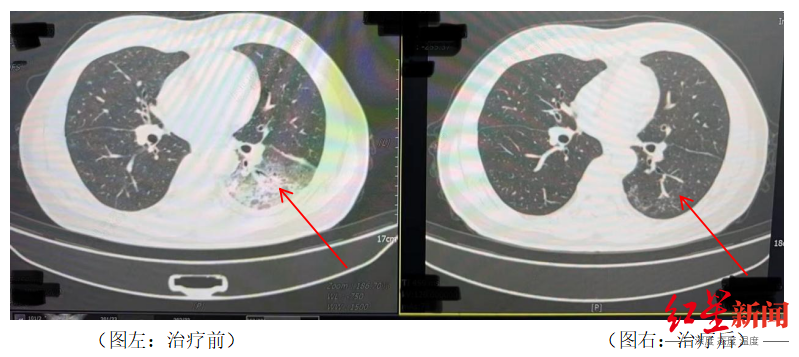

周先生治疗前后的肺部CT影像

2024年,55岁的长沙市民周先生(化姓)有2型糖尿病、2型糖尿病性肾病、慢性肾功能不全等多个既往史,因持续发热、寒战、咳嗽前往医院就诊,检查发现肺部存在严重感染,应用抗生素抗感染治疗后效果不佳,患者依然持续发热,还出现了神志淡漠的异常表现。医生询问发现,周先生此前驾车出差,因为天气热,他启动了久未清洗的车载空调,每天在车上的时间超过十个小时,回来后就出现了如上症状。经过检查,最终确诊为军团菌肺炎。